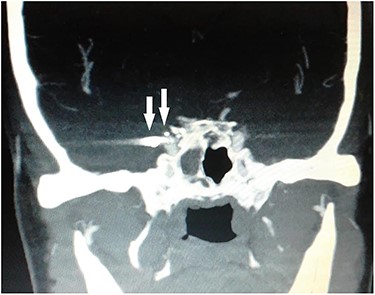

Computed tomography (CT) of the paranasal sinuses and angiography were requested on an urgent basis, which confirmed a diagnosis of pseudoaneurysm in her right CCA, adjacent to retained pellets (Figs 1–4). Also, her hemoglobin dropped from 11.5 to 8.4 gm over a 6-month period. Afterwards, she was referred to the interventional radiology department. She underwent stenting and coiling of her right internal carotid artery after which no further epistaxis happened for an uneventful year of follow-up.

CT scan coronal view showing right sphenoid sinus opacification with denudation of sphenoid sinus wall (arrow).